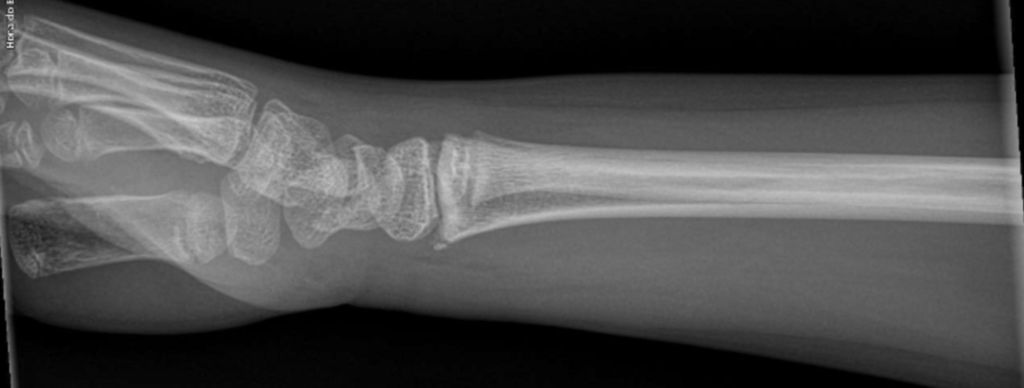

Fratura fechada

Fratura deslocada

Fratura articular

Fratura subperiostal

Fratura frisária